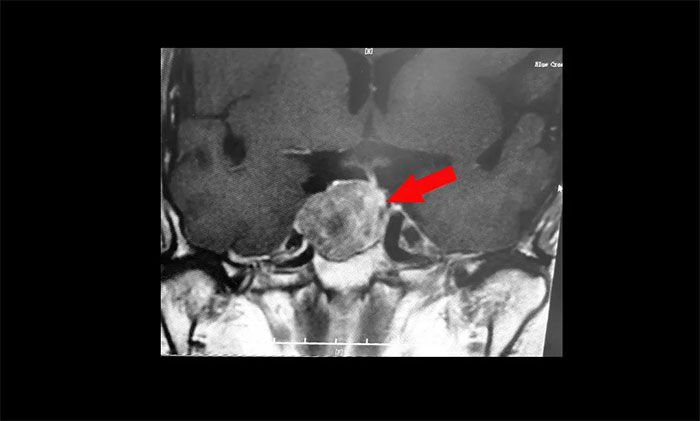

鞍区MRI平扫+增强显示:蝶鞍显著扩大,鞍区见肿块信号,大小约29*19*24mm;垂体柄明显缩短左偏;病变向鞍上生长,占据鞍上池,推移视交叉;向鞍旁生长,侵及右侧海绵窦,右侧海绵窦内颈内动脉被推压、包绕,右侧颈内动脉海绵窦段较对侧稍细。

▲ 肿瘤侵袭生长,包绕颈内动脉,knosp分级Ⅲ级

针对该患者,治疗方式就是手术切除肿瘤,减除肿瘤压迫。目前手术方式,主要有开颅手术切除肿瘤和经单鼻孔-蝶窦入路切除肿瘤。而该患者肿瘤如鸽子蛋大小,属于垂体大腺瘤,并且侵袭生长,侵及右侧海绵窦,右侧海绵窦内颈内动脉被推压、包绕,knosp分级Ⅲ级,向上已突破鞍隔压迫视神经、视交叉、下丘脑;向下侵蚀充满蝶窦。